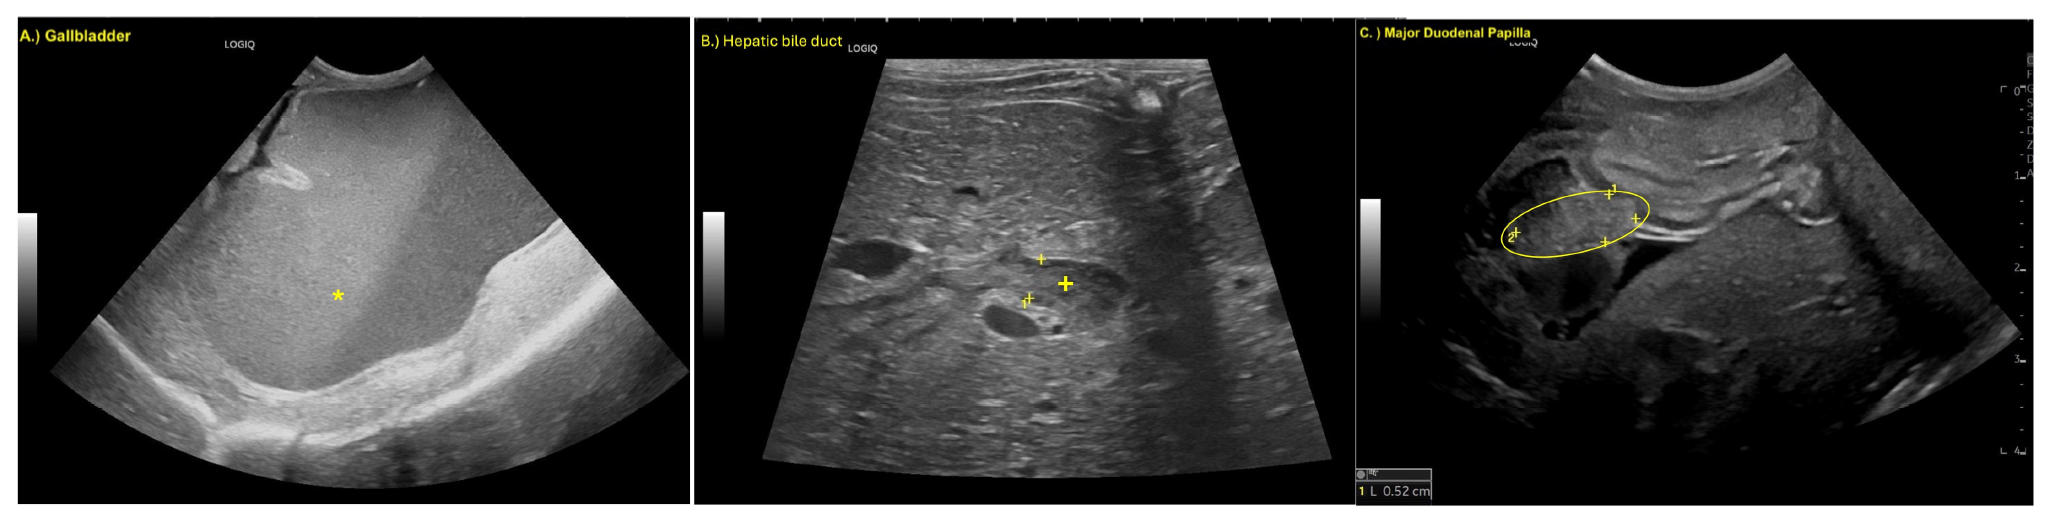

腹部探查显示胆囊和胆总管显著扩张,大小约为10×7厘米,肝管平均直径约8毫米(下图)。胆囊、胆囊管和胆总管的解剖结构已无法区分。

↑ 扩张的胆囊(GB),增大的胆管(CD)和胆总管(CBD)进入十二指肠(D),严重扩张的肝管(HD)和严重炎症的胰腺(P)。

此外,胆总管与十二指肠在十二指肠乳头水平的连接处严重扩张(下图)。

↑ 胆管(CD)和胆总管(CBD)与十二指肠(D)在十二指肠乳头(MDP)处的连接严重扩张,以及炎症的胰腺(P)。

胆囊和胆总管内充满了黄色渗出物(脓液和胆汁的混合物),在开始解剖时,渗出物开始从肝脏漏出(下图)。胰腺右侧出现严重炎症,主胰管扩张,也含有黄色渗出物。胃部为空且受压,可能是由于扩张的胆囊和胆总管的压迫效应所致。

↑ 胆囊(GB)和肝脏(L)渗出的黄色渗出物(YE)。